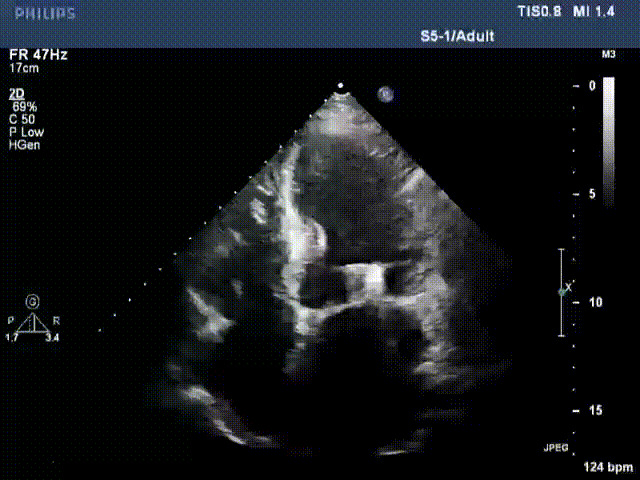

出院前隨訪超聲

接受治療的是一例器質(zhì)性重度二尖瓣反流(DMR)患者,主訴“反復(fù)活動后胸悶,氣促3年余”。術(shù)前超聲顯示,雙房增大,二尖瓣脫垂伴重度反流,輕度三尖瓣反流,輕度肺高壓,升主動脈增寬。手術(shù)經(jīng)股靜脈-房間隔入路,采用全身麻醉插管,在TEE和DSA引導(dǎo)下完成房間隔穿刺。置入JensClip瓣膜夾系統(tǒng)后,在左房調(diào)整瓣膜夾的位置和軸向,后進入左室,在TEE引導(dǎo)下捕捉二尖瓣前后瓣葉,并關(guān)閉瓣膜夾。經(jīng)TEE反復(fù)確認手術(shù)效果后最終鎖定并釋放瓣膜夾。術(shù)后即刻超聲顯示瓣膜夾位置穩(wěn)定,功能良好,術(shù)前二尖瓣反流4+,術(shù)后0反流,肺靜脈逆流和左房壓都顯著好轉(zhuǎn),手術(shù)圓滿成功(以上數(shù)據(jù)都來源于醫(yī)院的臨床記錄)。術(shù)后患者狀態(tài)良好,目前已安排出院。